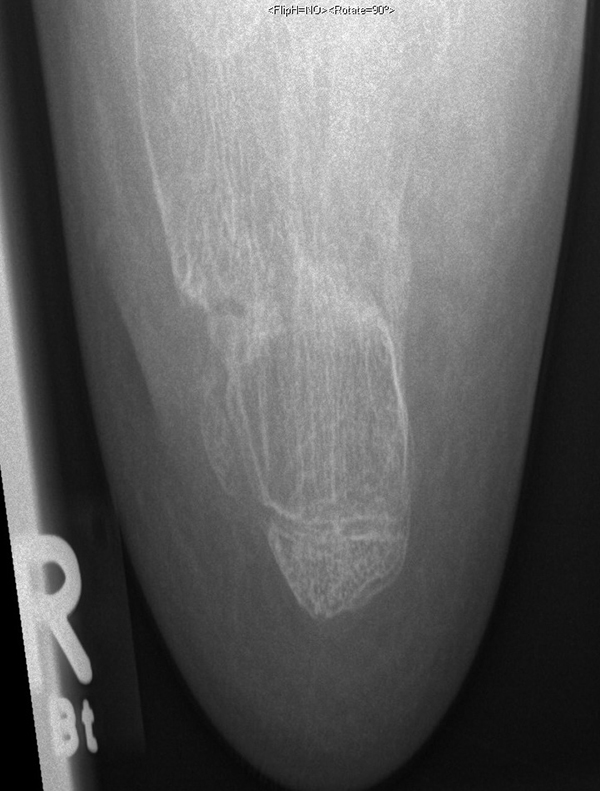

Abb. 8 a-g: Genua vara prä- und postoperativ versorgt mit Flex Tacks (a-b) und ein Genu valgum versorgt mit Eight Plate an der medialen Femurkondyle (c); Spitzfuß bei congenitalem Klumpfuß und einem Flat Top Talus mit präoperativem Röntgenbild seitlich und der deutlich nach dorsal stehender Tibia(d); intraoperative Bilder der Epiphysiodese mittels Eight Plate zur Wachstumslenkung der distalen Tibia in die Extension (e-f) und postoperativer Verlauf nach sechs Monaten mit regelrecht stehender Tibia über dem Talus durch die distale Extension (g).

Zum Lesen der Bildbeschreibung und zur Vollansicht bitte die Bilder anklicken. Bilder: A. Helmers.